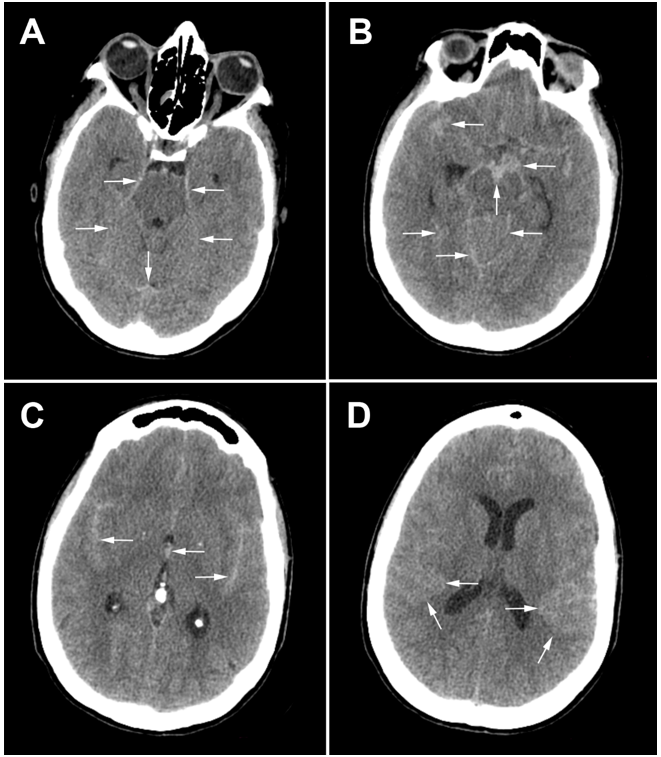

A 43-year-old hypertensive woman visited the emergency department of her local community for a sudden onset of headaches. On the physical exam, she was hemodynamically stable with a blood pressure of 150/90 mm Hg. Her Glasgow Coma Scale (GCS) score was 15/15, and her pupils were isochoric and reactive to light and accommodation. No seizures, visual disturbance, sensorimotor deficit, or fever were noticed. A brain CT showed diffuse SAH with blood in basal cisterns, cerebellar tentorium, and temporal sulci associated with discreet brain edema (Figure 1). The SAH was graded as Hunt and Hess grade 1 and Fisher CT grade 3. Given brain CT results and hypertensive peak, aneurysmal SAH was suspected. Thus, the patient was referred to the neurosurgery department. On admission, her GCS score was 14/15, and she had neck stiffness, photophobia, and phonophobia. In addition, left-sided ptosis and mydriasis were elicited, suggesting left oculomotor nerve palsy. The DSA was unavailable at our institution (a public hospital), and the cost was prohibitive at private facilities. So, a brain CTA with 3D reconstruction was performed, which revealed a 10 mm left paraclinoid aneurysm and a 9 mm left PCA aneurysm (Figure 2, Figure 3, Figure 4). The initial therapeutic strategy was maintaining systolic pressure between 120 and 140 mm Hg using an antihypertensive drug and preventing vasospasm using nimodipine. Since endovascular therapy was unavailable, surgeons chose surgical clipping. Therefore, the patient was transferred to the operating room, placed in the dorsal decubitus position, and the head right turned 60 degrees. Then, a left fronto-temporo-pterional craniotomy was performed. The paraclinoid aneurysm was oriented behind and was wide-necked. Its sac was bilobed and close to the pituitary fossa, the posterior communicating artery (PCOA), the superior wall of the cavernous sinus, and the left clinoid processes. Thus, the operating field was too narrow, and clipping might injure surrounding structures. Therefore, surgeons preferred muscle wrapping instead of clipping. The posterior aneurysm had a wide neck involving the left SCA and PCA origins and was close to the P1 and P2 segments. However, there was a good safety margin to clip the neck without interrupting the blood flow in the SCA and the PCA, which has been done. Despite successful surgery, the patient remained unconscious. On the sixth postoperative day, a brain CT was performed. It revealed a ventricular hemorrhage with diffuse cerebral edema, graded as Hunt and Hess 5 and Fisher CT grade 4. Thus, an external ventricular drain was urgently placed. Unfortunately, the patient succumbed to this event.

Figure 1.Brain CT scan slices: white arrows indicate the subarachnoid hemorrhage in basal cisterns, cerebellar tentorium, and temporal sulci.